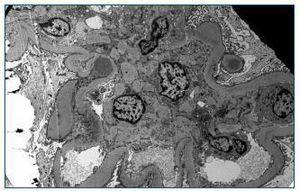

Dada la rápida progresión de la IR, sin haber podido aclarar la etiología, se indica la realización de una biopsia renal en la que se objetivan 21 glomérulos, seis esclerosados y los restantes con expansión mesangial glomerular, apreciándose en uno de ellos una semiluna. Engrosamiento de la membrana basal tubular e infiltrado inflamatorio intersticial moderado, con predominio de células plasmáticas, polimorfonucleares neutrófilos y linfocitos. El estudio de inmunofluorescencia es negativo. Con microscopia electrónica se demuestra engrosamiento difuso de la membrana basal glomerular, con la presencia de depósitos electrón-densos subepiteliales que configuran los típicos humps (figura 1).

Con estos hallazgos se llega al diagnóstico de glomerulonefritis de origen postinfecciosa (GNPI) complicando una nefropatía diabética (ND).

Figura 1. M.E: GN Postinfecciosa. Presencia de depósitos electrón-densos subepiteliales (humps).